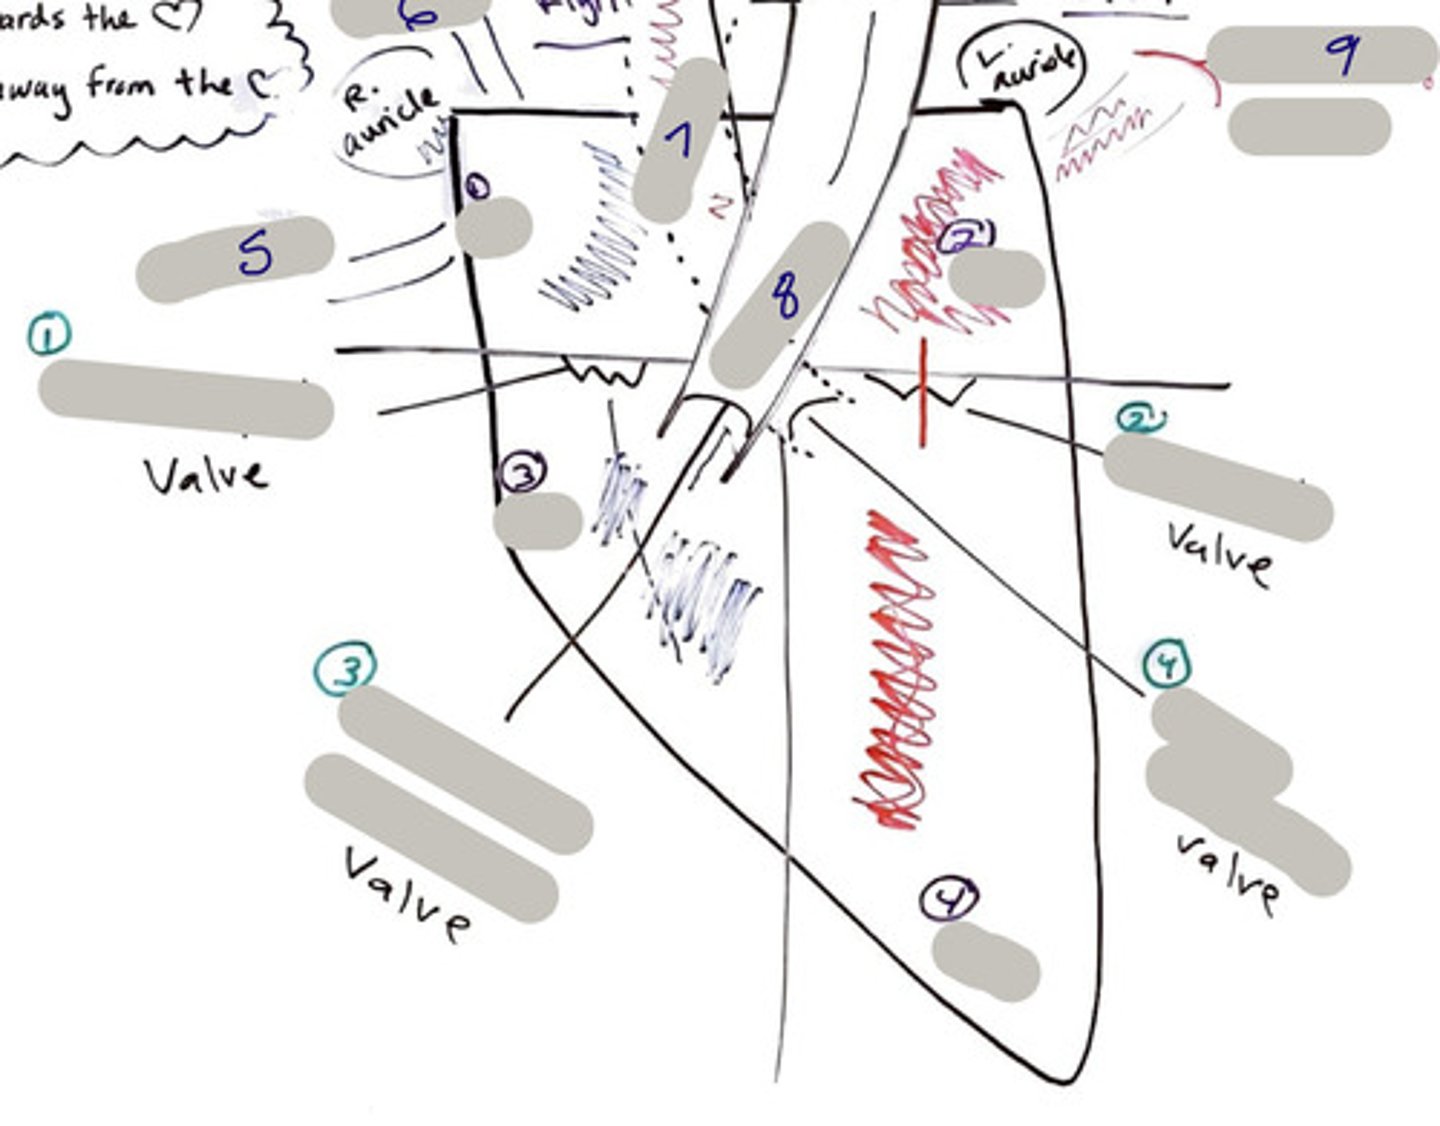

Tricuspid Valve (Right Atrioventricular Valve)

1-valve

Bicuspid valve (Left Atrioventricular Valve)

2-valve

Pulmonary Semilunar Valve

3-valve

Aortic Semilunar Valve

4-valve

Right Atrium

1-chamber

Left Atrium

2-chamber

Right Ventricle

3-chamber

Left Ventricle

4-chamber

Inferior Vena Cava

5-A vein that is the largest vein in the human body and returns blood to the right atrium of the heart from bodily parts below the diaphragm.

Superior Vena Cava

6-A vein that is the second largest vein in the human body and returns blood to the right atrium of the heart from the upper half of the body.

Aorta

7-The large arterial trunk that carries blood from the heart to be distributed by branch arteries through the body.

Pulmonary Trunk

8-carries blood from right ventricle to pulmonary arteries

Pulmonary veins

9-a vein carrying oxygenated blood from the lungs to the left atrium of the heart.